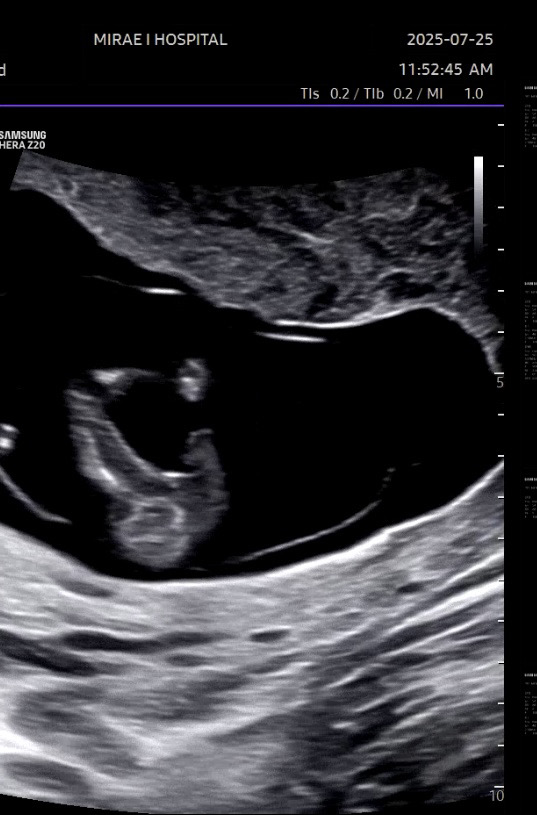

12주차 초음파 아예 성기가 없을수도 있나요?

12주차 초음파보다가 아기 다리 사이를 봤는데 원래 이맘때쯤이면 다 고츄가 있다고 알고있었거등요 근데 사진처럼 아예 없을수도 있나요??

저도 이번에 12주차 초음파 이각도에 암것도 없이 매끈하더라구요.선생님이 공주일수도있겠네요 하셨어요.

네~~ 저희 첫째 둘째 둘다 딸인데 둘다 그 시기에 매끈햇어요 ㅎㅎㅎㅎ